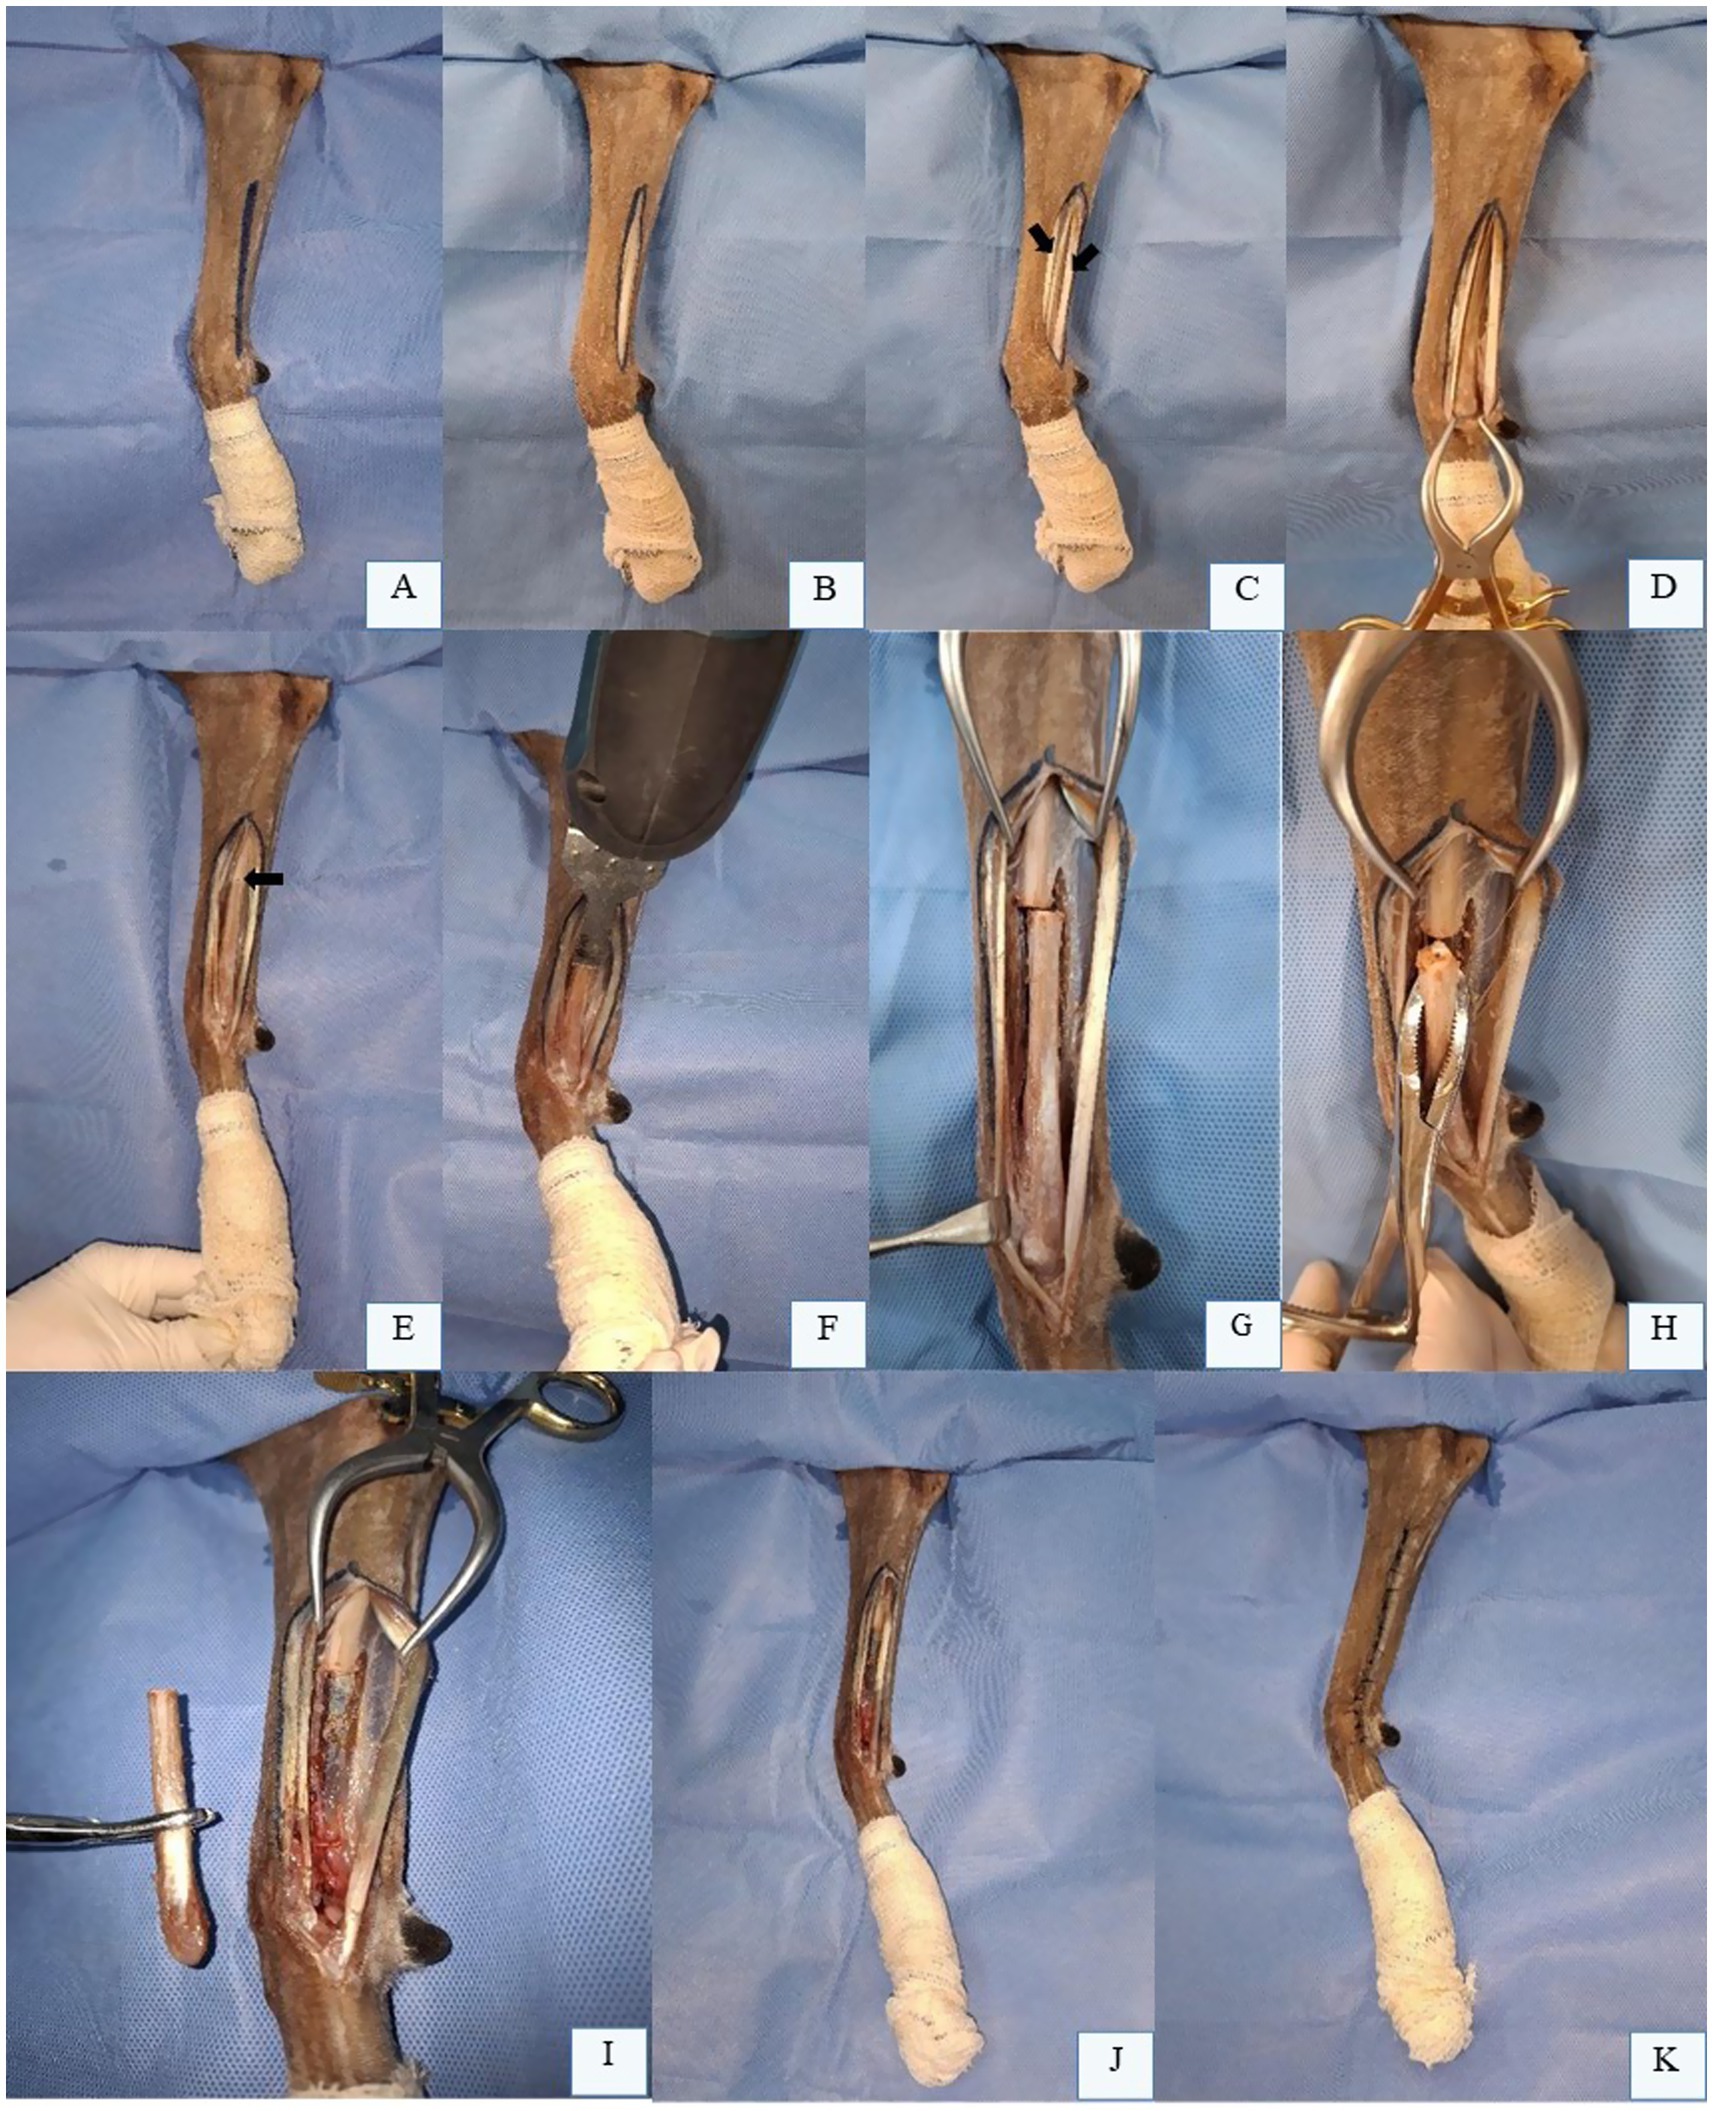

Ulnar OSA most commonly affects the distal ulna, though other regions may also be involved (59). Bone biopsy is typically performed postoperatively, as most ulnar neoplasms are malignant, and tumor type rarely alters the surgical approach. Minimum surgical margins of 3.0 cm are recommended, which can be accessed via CT or nuclear scintigraphy. Evaluation of the integrity of the radius is mandatory; if compromised, a more extensive surgical approach is required (59). Partial ulnectomy (Figure 3) generally yields good to excellent clinical outcomes in dogs and cats, even without post-resection reconstruction or stabilization, allowing near-normal limb function; the use of this technique has recently been described (28, 29).

Figure 3

X-ray images show a limb with a noticeable abnormality or growth around the bone in two different views, labeled A and B. A subsequent image, labeled C, displays a removed tissue specimen placed on a blue surgical drape.

Figure 3. Partial ulnectomy. (A) Radiographic image in laterolateral projection of the left radius and ulna of a canine patient with OSA in the distal ulna. (B) Radiographic image in laterolateral projection of the left radius and ulna of a canine patient after the partial ulnar ostectomy. (C) Fragment of the distal ulna of a dog with OSA after partial ulnectomy. Dr. Renato Dornas – Small Animal Surgery Service, Universidade Federal de Minas Gerais (UFMG), Belo Horizonte, Brazil; none of the images have been published in any other scientific work.

The patient is positioned in lateral recumbency with the affected limb uppermost, clipped and aseptically prepared for partial ulnectomy. A skin incision is made along the lateral aspect of the ulna, extending from the mid-diaphysis to the styloid process (Figure 4A). Subcutaneous tissues are dissected (Figure 4B), and the antebrachial fascia is identified and incised (Figure 4C). The tendons of the lateral digital extensor muscle (cranially) and lateral ulnar muscle (caudally) are visualized and retracted to expose the ulnar surface. For enhanced exposure, the origin of the abductor pollicis longus muscle may be partially elevated from the cranial border of the distal ulna (Figure 4D). The approach can be extended distally to expose the carpal and metacarpal bon es if required. After confirming adequate margins (black arrow, Figure 4E), osteotomy is performed using an oscillating saw under continuous saline irrigation (Figures 4F,G). The ulnar fragment is removed with bone forceps (Figure 4H) and disarticulated from the carpus (Figure 4I). Intraoperative assessment of radiocarpal joint stability is critical following excision of the lateral styloid process. In most dogs, reconstruction of the bony column is unnecessary (Figure 4J). Closure involves suturing the antebrachial fascia, subcutaneous tissue, and skin in layers (Figure 4K) (28, 59).

Figure 4

Sequential surgical procedure images on a bone, labeled A to K. Images A through C show markings on the bone. Images D and E display clamps and forceps positioning. Image F includes cutting tools and retractors in action. G to I highlight various manipulation of the bone, including separation and removal of a segment. Images J and K show the bone with bandaging, possibly indicating completion or healing stages. Blue surgical drape is visible in each scene.

Figure 4. Partial Ulnectomy in the Left Thoracic Limb (LTL) of a Canine Cadaver in Right Lateral Recumbency. (A) Skin incision marking along the lateral aspect of the ulna, from the mid-diaphysis to the styloid process. (B) Subcutaneous tissue dissection. (C) Visualization and incision of the antebrachial fascia, with identification of the lateral digital extensor tendon (cranial arrow) and lateral ulnar tendon (caudal arrow). (D) Ulnar surface exposed after retraction of fascia and tendons. (E) Osteotomy site pre-marked with an oscillating saw (black arrow). (F) Ulnar diaphyseal osteotomy using an oscillating saw. (G) Ulna after complete cortical transection. H: Bone forceps grasping the osteotomized ulnar segment prior to distal disarticulation. (I) Fully removed ulnar segment. (J) Remaining ulna post-osteotomy, requiring no reconstruction or stabilization. (K) Final surgical site appearance after partial ulnectomy. Original images captured by the authors during a cadaveric surgical demonstration for academic purposes; none of the images have been published in any other scientific work.